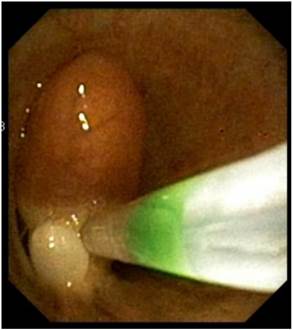

Figure 8

Removal of endobronchial tumor with loop.

J Cancer Image